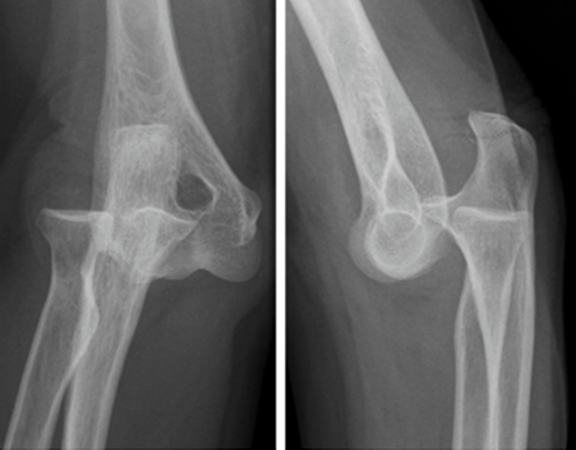

LUXAÇÃO DO COTOVELO

Luxação é a perda de contato entre dois ossos que costumavam estar sempre em contato íntimo e contínuo através da cartilagem. Esse tipo de luxação não é muito comum em cotovelos por terem uma articulação estável, mas quando acontece é, geralmente, quando o indivíduo sofre um trauma, queda ou pancada de alto impacto. Diferente da luxação de ombro, a de cotovelo pode acompanhar fraturas associadas e é de extrema importância que se faça uma radiografia antes de colocar a articulação no lugar. Diante do quadro procure imediatamente um pronto-socorro para os primeiros atendimentos e logo em seguida um médico ortopedista especializado para que ele possa averiguar a situação e dizer qual o tratamento mais adequado. ⠀